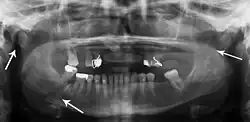

Nondisplaced fracture of the mandible

Panoramic radiography

Panoramic radiographs are tomograms where the mandible is in the focal trough and show a flat image of the mandible. Because the curve of the mandible appears in a 2-dimensional image, fractures are easier to spot leading to an accuracy similar to CT except in the condyle region. In addition, broken, missing or malaligned teeth can often be appreciated on a panoramic image which is frequently lost in plain films. Medial/lateral displacement of the fracture segments and especially the condyle are difficult to gauge so the view is sometimes augmented with plain film radiography or computed tomography for more complex mandible fractures.

Research has shown that panoramic radiography is similar to computed tomography in its diagnostic accuracy for mandible fractures and both are more accurate than plain film radiograph.[12] The indications to use CT for mandible fracture vary by region, but it does not seem to add to diagnosis or treatment planning except for comminuted or avulsive type fractures,[13] although, there is better clinician agreement on the location and absence of fractures with CT compared to panoramic radiography.[14]